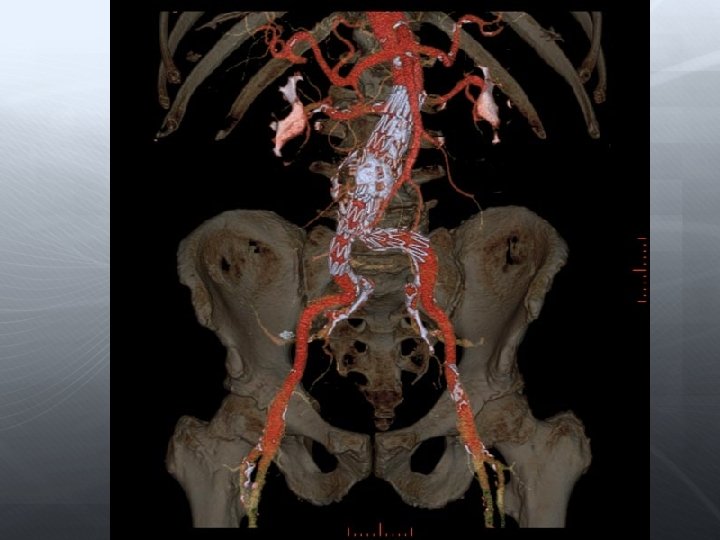

Darlık Oklüzyon Aorto-iliak Femoral-popliteal Infrapopliteal

Aorta-İliak